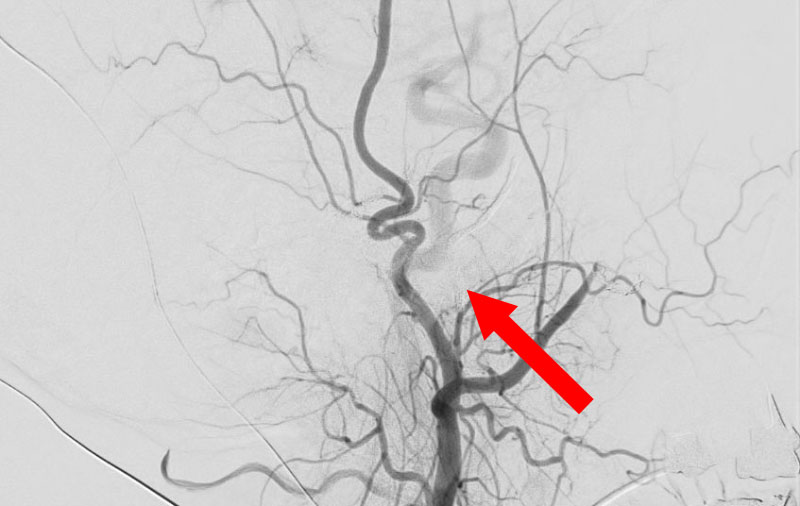

左中大脳動脈瘤破裂

No.1596 手術前